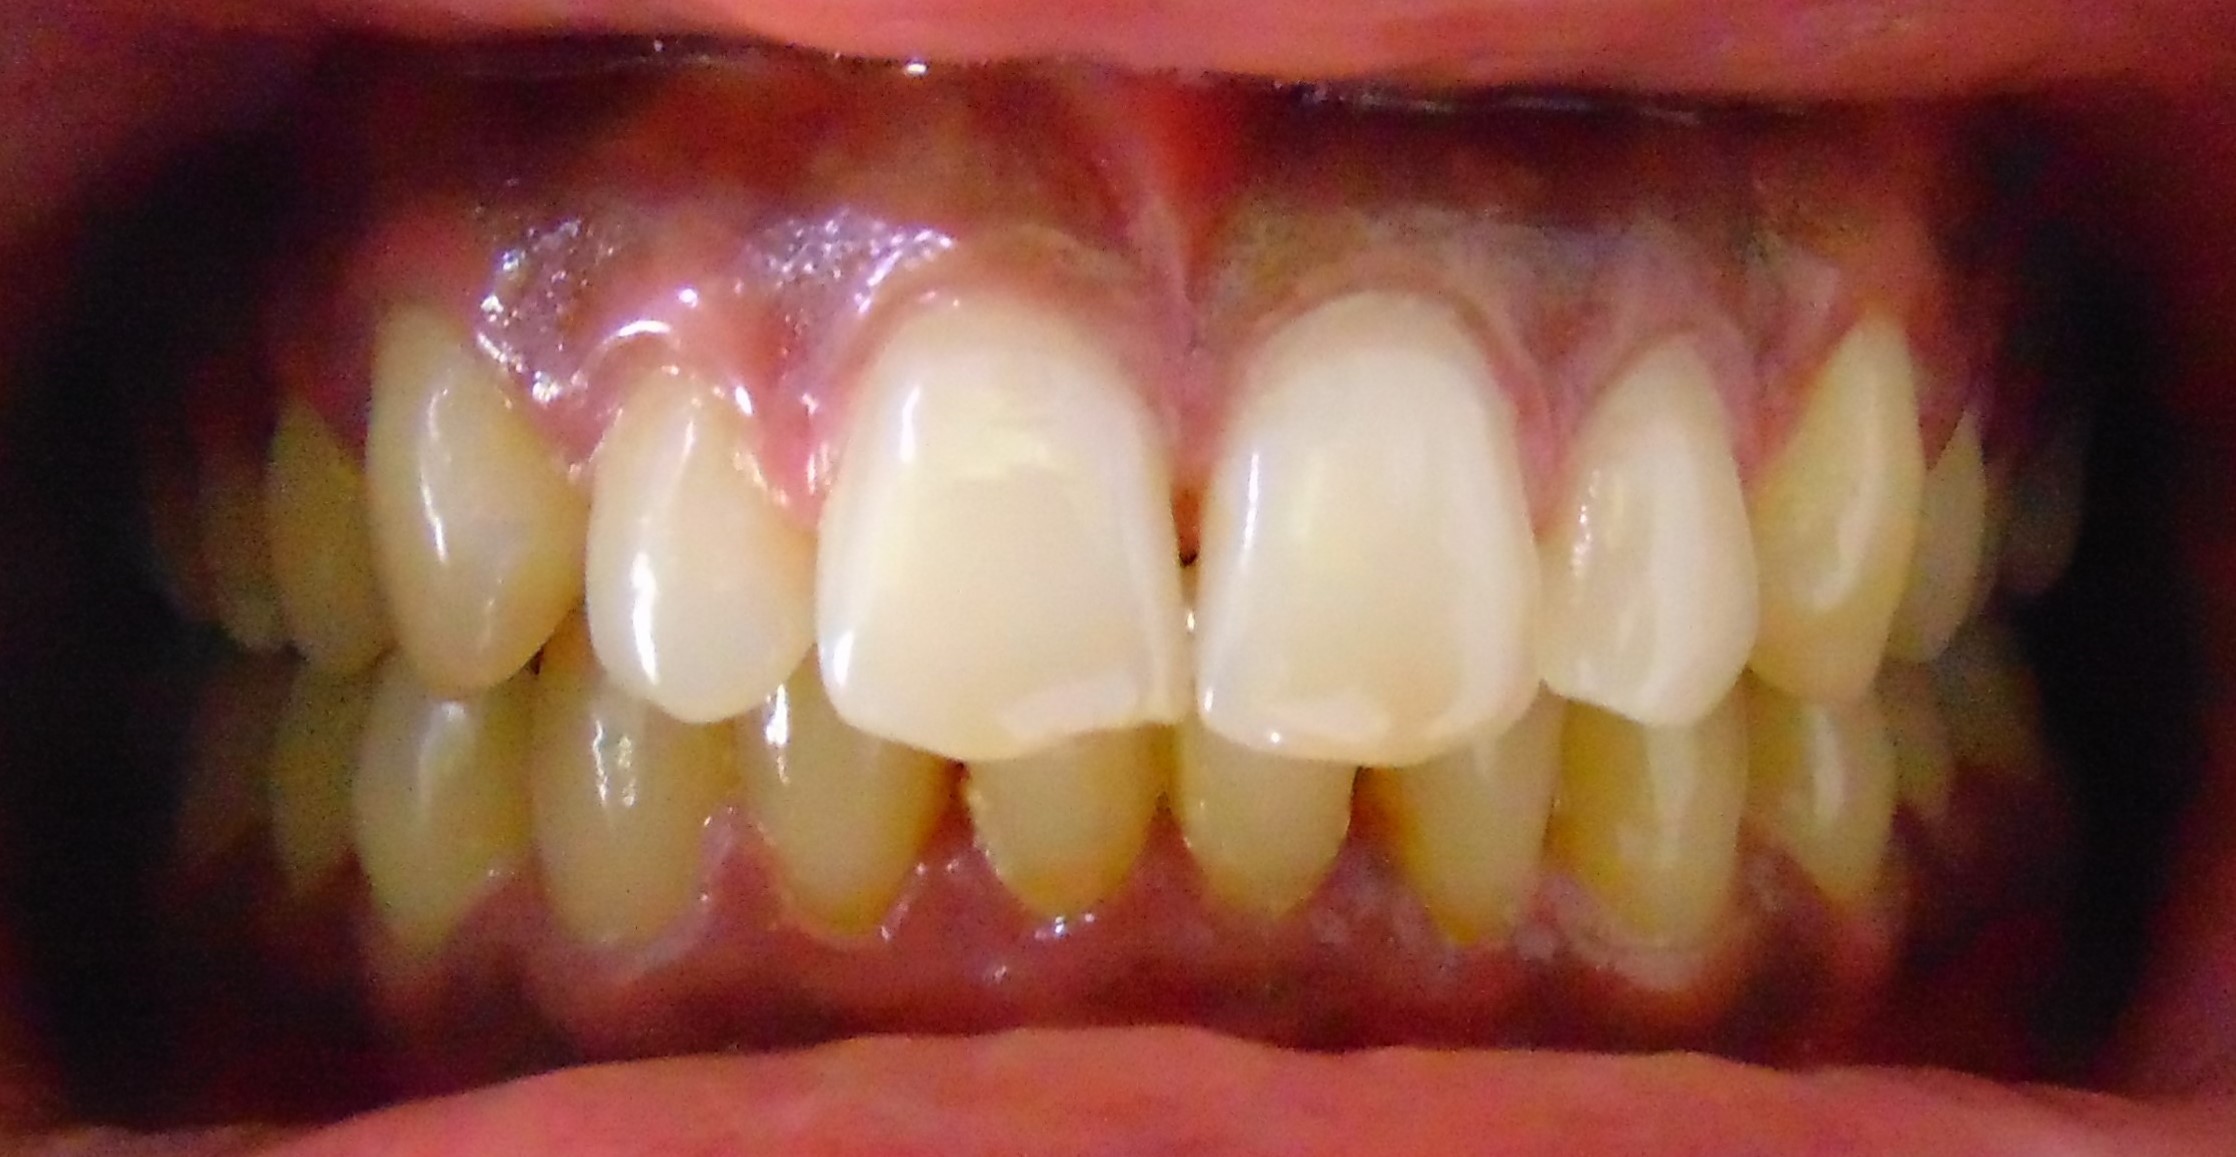

Before

After

Image 1